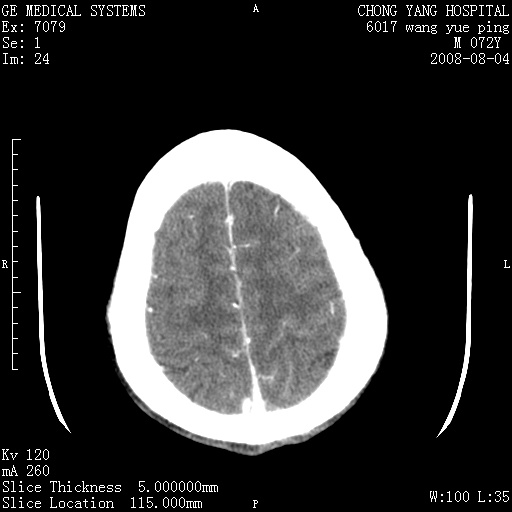

标题: CT14987:M72Y,头痛头昏,BP220/110. [打印本页]

标题: CT14987:M72Y,头痛头昏,BP220/110.

1)考虑左侧小脑脑梗塞。2)脑白质病。3)脑萎缩。4)双侧鼻腔新生物(息肉?)并阻塞性副鼻窦炎。

1.左侧小脑大面积梗塞;2.左侧基底节区腔梗;3.白质疏松;4.脑萎缩;5.慢性副鼻窦炎

小脑左侧病灶呈扇形分布,增强后未见明显瘤体样节结影,病变区未见强化。

支持:左侧小脑脑梗塞梗塞表现

另:脑白质病。脑萎缩。双侧鼻腔新生物(息肉?)并阻塞性副鼻窦炎。

1)考虑左侧小脑脑梗塞,建议治疗后复查除外其他,左基底节区腔隙性脑梗塞2)脑白质变性3)脑萎缩。4)双侧鼻腔新生物(息肉?)并阻塞性副鼻窦炎。